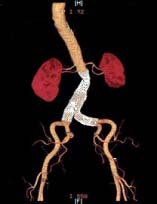

Imagem (Aorta, com largo aneurisma abdominal)

Tomografia Computadorizada: é o teste mais preciso para fazer uma imagem de aneurisma aórtico. Demonstra claramente o tamanho e a extensão do aneurisma aórtico e sua relação com as artérias renais e ilíacas.

Imagem (Tomografia computadorizada)